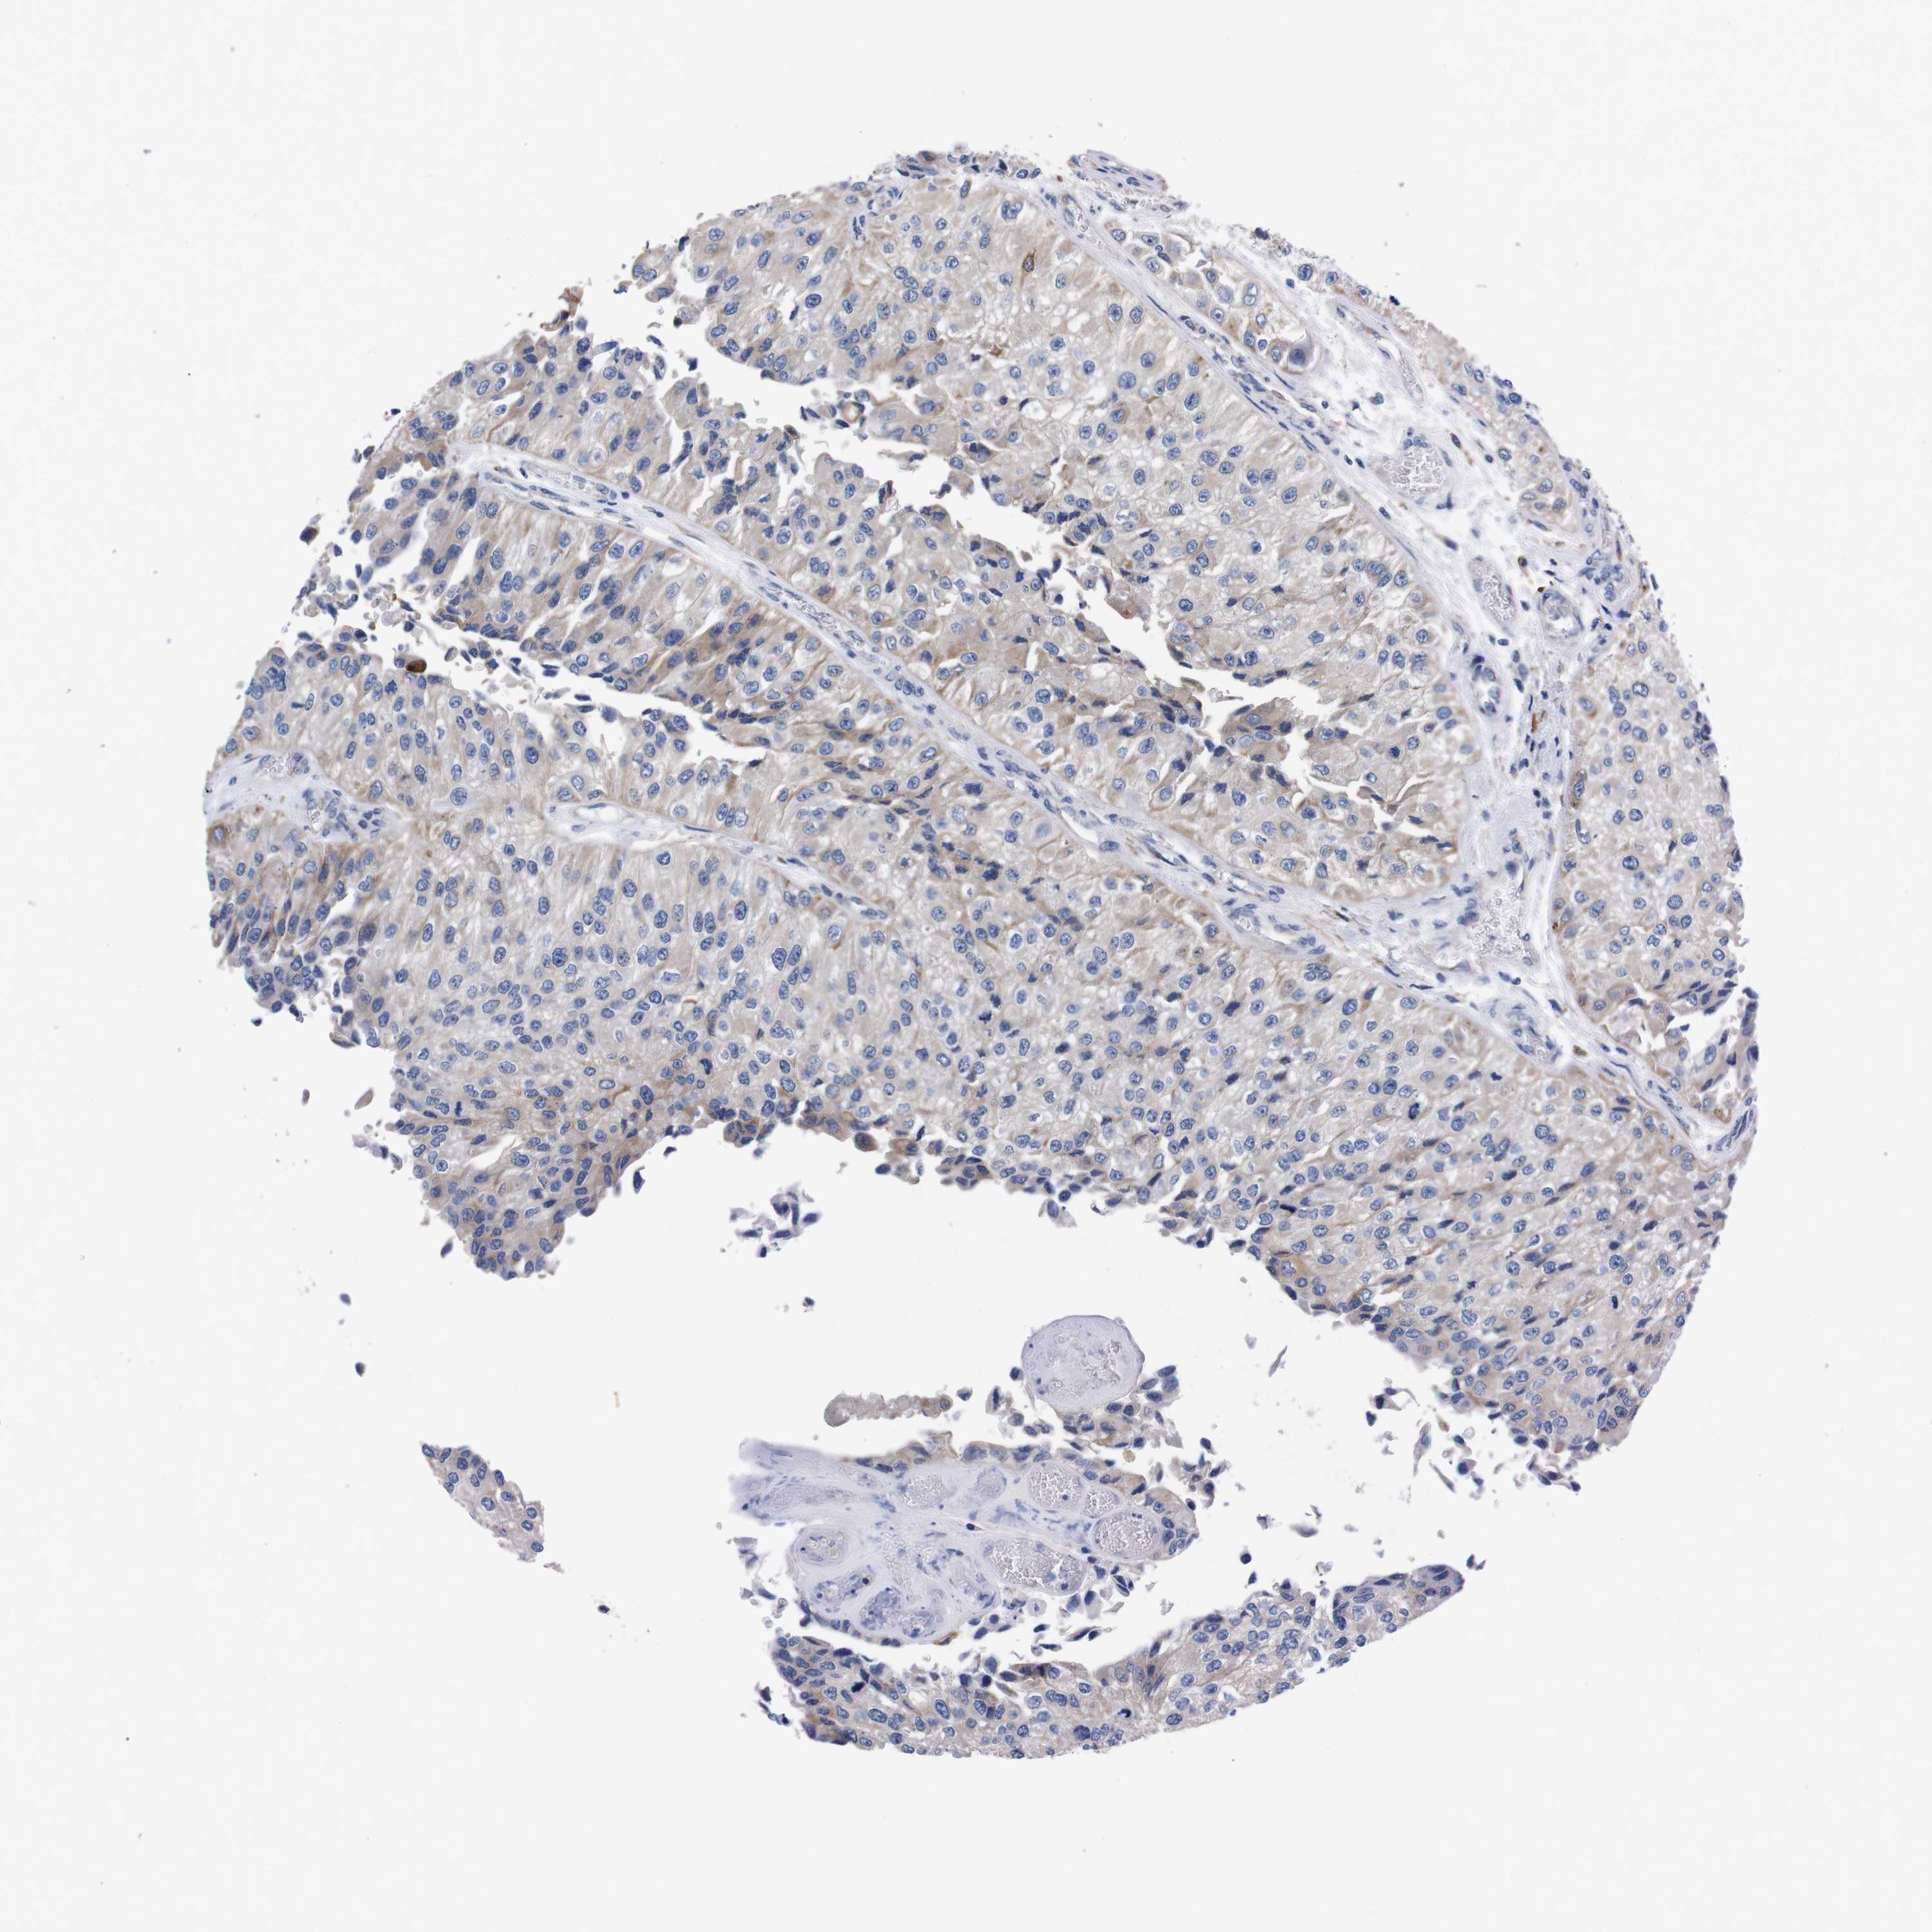

UROTHELIAL CANCER - Protein expressioni

A mouse-over function shows sample information and annotation data. Click on an image to view it in a full screen mode. Samples can be filtered based on level of antibody staining by selecting one or several of the following categories: high, medium, low and not detected. The assay and annotation is described here.

Note that samples used for immunohistochemistry by the Human Protein Atlas do not correspond to samples in the TCGA dataset.

Antibody stainingi

Antibody staining in the annotated cell types in the current human tissue is reported as not detected, low, medium, or high, based on conventional immunohistochemistry profiling in selected tissues. This score is based on the combination of the staining intensity and fraction of stained cells.

Each image is clickable and will lead to virtual microscopy that enables deeper exploration of all samples and also displays staining intensity scores, fraction scores and subcellular localization as well as patient and tissue information for each sample.

Antibody HPA013994

Antibody HPA013995

Staining

High

Medium

Low

Not detected

Intensity

Strong

Moderate

Weak

Negative

Quantity

>75%

75%-25%

<25%

None

Location

Nuclear

Cytoplasmic/membranous

Cytoplasmic/membranous,nuclear

Urothelial carcinoma, Low grade

Urothelial carcinoma, High grade